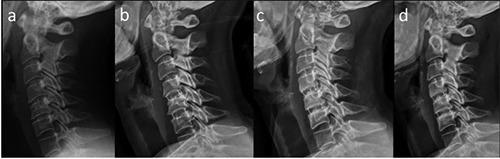

Poly-ether-ether-ketone (PEEK) cages have lower modulus of elasticity when compared with Titanium (TTN) cages. This suggests that PEEK-cages could show a lower rate of subsidence after anterior cervical discectomy-fusion (ACDF) and might lead to a lower loss of correction. We investigated the one to five year-results of standalone PEEK-TTN-porous coated cages in a patient cohort from 2014 to 2017. The patients underwent single-level ACDF for disc herniation and degenerative discopathy. Clinical and radiological outcome were assessed in 50 eligible patients after a mean of 27 months. Results: Solid arthrodesis was found in 84%. Neck disability index (NDI), and visual analogue scale (VAS) of neck and arm show comparable results to the literature. Conclusions: Clinical and radiological outcomes of ACDF with PEEK-body-cages with a porous coated surface show good bony integration. The modulus of elasticity, design, shape, size, cage surface architecture, as well as bone density, endplate preparation, radical microdiscectomy and distraction during surgery should be considered as important factors influencing the clinical results. One main advantage, over titanium cages, is the absence of MRI artifacts, allowing an excellent postoperative follow-up.

与钛(TTN)椎间融合器相比,聚醚醚酮(PEEK)椎间融合器的弹性模量更低。这表明,在颈椎前路椎间盘切除融合术(ACDF)后,PEEK椎间融合器可能显示出更低的下沉率,并可能导致更低的矫正丢失率。我们调查了2014年至2017年一组患者中独立使用的PEEK-TTN多孔涂层椎间融合器1至5年的结果。这些患者因椎间盘突出症和退行性椎间盘病接受了单节段ACDF。对50例符合条件的患者在平均27个月后进行了临床和影像学评估。结果:84%实现了坚固的椎间融合。颈部残疾指数(NDI)以及颈部和手臂的视觉模拟量表(VAS)结果与文献报道相当。结论:采用多孔涂层表面的PEEK椎间融合器进行ACDF的临床和影像学结果显示出良好的骨融合。弹性模量、设计、形状、尺寸、椎间融合器表面结构,以及骨密度、终板准备、彻底的显微椎间盘切除术和手术中的牵引应被视为影响临床结果的重要因素。与钛椎间融合器相比,一个主要优点是不存在MRI伪影,便于进行出色的术后随访。